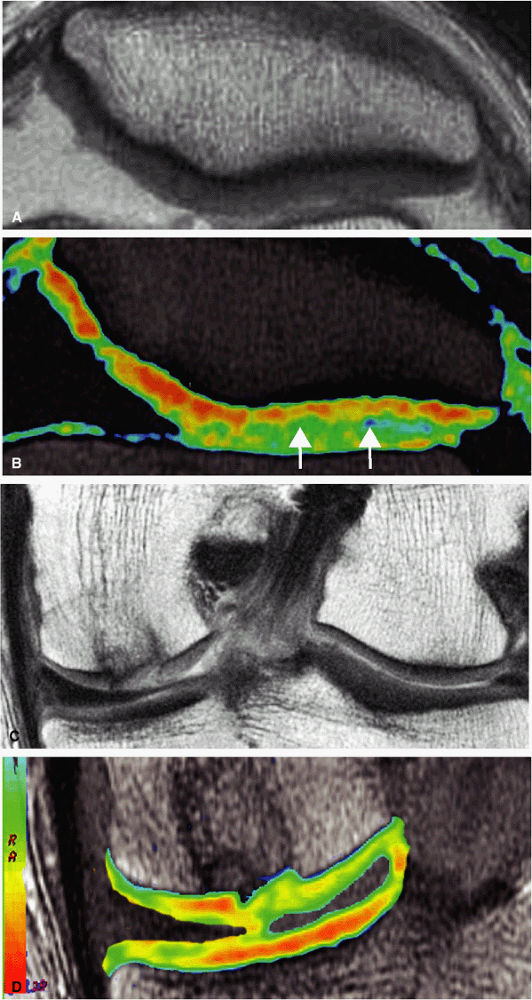

![]() |

FIGURE 1.18 ● Spin-echo, 8 echoes (10 to 80 msec). Note the signal attenuation in the patellar cartilage. This type of sequence is used to produce cartilage T2 color maps.

FIGURE 1.19 ● Color map (A) showing T2 values from 20 msec in red to 75 msec in blue, with calculated T2 values from the region of interest (ROI). ROI #1 green curve (B) shows the 8-echo signal pattern, and the red curve shows the calculated monoexponential fit.

FIGURE 1.20 ● Clinical examples of T2 mapping at 3 T. Color map showing T2 values from 25 msec in red to 75 msec in blue. (A, B) Osteoarthritis (arrow) is not visible on the conventional T2 image (A). (C, D) Autologous osteochondral implant (mosaicplasty) of the medial femoral condyle with mild prolongation of T2 values. (Courtesy H.G. Potter, HSS, NY)